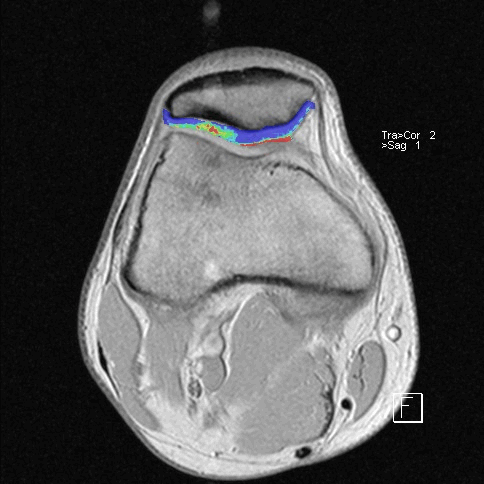

МРТ коленного сустава

Особая диагностическая ценность МРТ коленного сустава состоит в получении исчерпывающей картины дегенеративно-дистрофических изменений (хронические артриты и остеоартрозы, повреждения суставных поверхностей) и возможности визуализации самых мелких травм (разрывы связок, сухожилий, переломы), визуализация хряща с последующим его картированием для определения дистрофических и травматических изменений.

Дистрофические изменения суставного хряща надколенника (с использованием опции «картирования хряща»)

МРТ помогает с большой точностью установить полный или же частичный разрыв мениска, прекрасно и наглядно отображает состояние связок коленного сустава. При диагностировании передней крестообразной связки МРТ показывает разрывы ясно и четко в 96%. Магнитно-резонансная томография наглядно демонстрирует не только разрывы сухожилий, но и гораздо более тонкие проблемы, возникающие во внутренней структуре, сопряженные с воспалением или рубцеванием тканей, которые при неблагоприятном прогнозе могут вызвать определенные хронические заболевания.